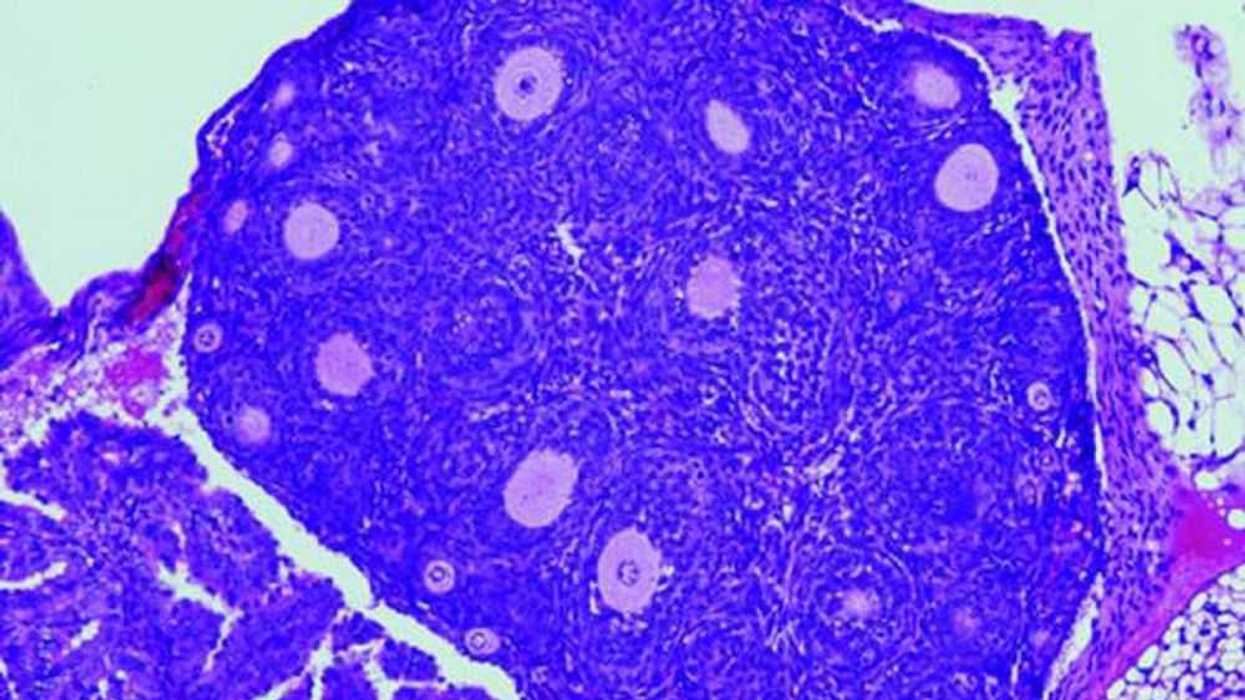

En la imagen se muestra la reducción en el número de folículos ováricos (causante de la insuficiencia ovárica prematura) en los ratones con la variante "humanizada" de una proteína. Imagen cedida por el Centro de Investigación del Cáncer (CSIC-USAL). EFE.

Cuando el óvulo se prepara para ser liberado en la ovulación, las células de la granulosa que lo rodean secretan un líquido folicular que crea una cavidad; esa masa de tejido, líquido y óvulo, recibe el nombre de "folículo de Graaf", ha explicado el CSIC en una nota de prensa difundida hoy.

Los investigadores, que han publicado los resultados de su trabajo en la revista Cancer Research, han demostrado en un modelo de ratón el papel clave que cumple la mutación genética de un solo gen en la iniciación y desarrollo de los tumores de células granulosas de adulto (AGCT), un tipo de cáncer de ovario.